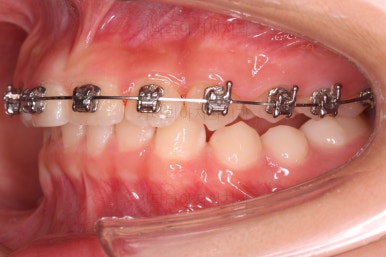

아랫니도 바로 교정장치를 부착하고, 교정장치를 통해 윗니와 아랫니를 끌어주고 철사를 이리저리 디자인해서 힘을 주고, 다양한 부가적인 부착물들을 활용하기로 했어요.

과개교합, 옥니, 앵글씨 2급 부정교합 모두 좋아지고 있어요.

앞니 각도가 매우 좋아졌고요.(옥니 개선) 위아래 앞니가 덮는 정도도 개선이 되었어요.(과개교합, 딥바이트)

엉성했던 어금니 맞물림도 매우 좋아졌어요.(앵글씨 2급 부정교합 개선)